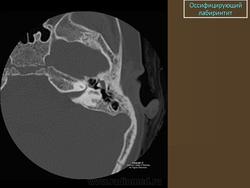

Оссифицирующий лабиринтит